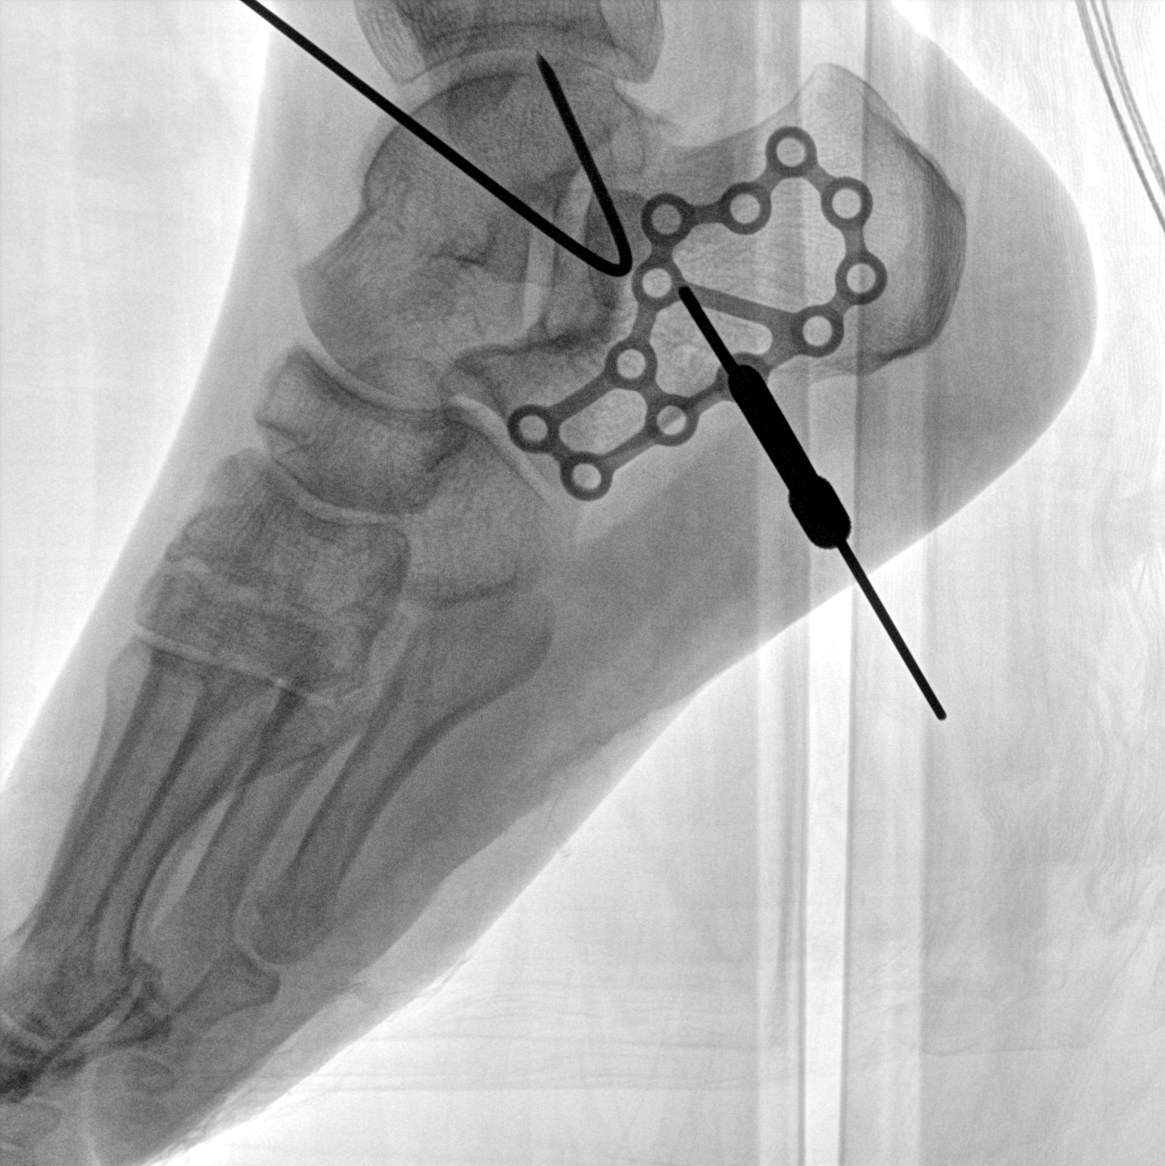

成像清晰、操作簡易、擺位便捷,主要適用于骨科、脊柱外科、矯形外科、創傷骨科及手術室等,能大幅度提升手術水準,降低手術風險和并發癥的概率。

術中三維成像和橫斷面圖像提供多角度的手術診斷信息,輔助醫生進行術中評估判斷,諸如骨折復位情況和內植入螺釘的尺寸和位置,輔助手術更好地完成。

提供更大的術中三維成像視野,采集更多圖像信息,可一次拍全全段頸椎、全段腰椎、七節胸椎、雙側骶髂關節、股骨頭及單側盆骨。